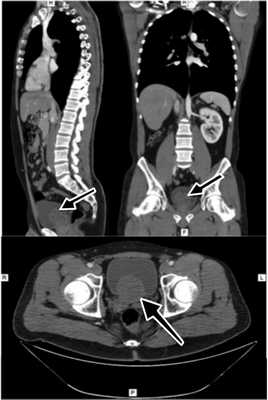

При компьютерной томографии (КТ) органов мочевыделительной системы диагноз агенезии правой почки был подтвержден, в проекции правого семенного пузырька выявлена киста диаметром 25 мм (рис. 5). Рисунок 5. КТ пациента В. Стрелкой указана киста семенного пузырька, пролабирующая в полость мочевого пузыря.